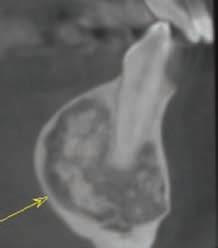

Cone-Beam Computed Tomography

Cone-beam computed tomography (CBCT) has become an essential tool in the field of dentistry, as it offers a highquality, 3-dimensional (3D) image.25 It is superior to bone sounding and conventional 2-dimensional radiography in the assessment of CEJ and bone morphology, as well as detecting abnormal root anatomy and bony dehiscence or fenestrations.13 Furthermore, it is more comfortable for patients and less invasive than bone sounding.26 Leung and colleagues reported on the greater accuracy of CBCT in identifying the CEJ than identifying alveolar bone margin.26 This was due to the fact that the CEJ is the junction between enamel and cementum, which have different densities, and the latter is the interface between cementum and bone, which have similar densities. In addition, greater accuracy was reported in detecting bone fenestration than dehiscence.

Grimard and colleagues reported a strong correlation between CBCT and direct surgical measurements of the hard tissues.27 Although CBCT was found to underestimate the distance from CEJ to the base of bone defect, it precisely estimated the distance between CEJ and alveolar crest. In contrast, intraoral PA radiographs were found to be less reliable than CBCT, as they underestimated the measurements of all investigated parameters considerably.27 Batista and colleagues suggested the use of CBCT for the diagnosis and presurgical planning of APE cases, as it provides accurate measurements related to the CEJ and alveolar bone crest, in addition to the actual anatomic crown length.4